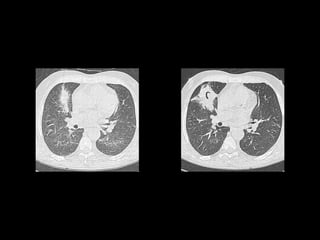

ASPERGILOSIS INVASIVA

• Pacientes neutropénicos.

• SIDA.

• Manifestaciones clínicas:

• Traqueobronquitis.

• Bronquiolitis.

• Bronconeumonía.

ASPERGILOSIS INVASIVA • Pacientesneutropénicos. • SIDA. • Manifestaciones clínicas: • Traqueobronquitis. • Bronquiolitis. • Bronconeumonía. Spectrum of Pulmonary Aspergillosis: Histologic, Clinical, and Radiologic Findings Tomás Franquet, Nestor L. Müller, Ana Giménez, Pedro Guembe, Jesus de la Torre, and S. Bagué RadioGraphics 2001 21:4, 825-837

• #29 Invasive bronchiolar aspergillo- sis in a patient who had undergone bone marrow transplantation. (a) Thin-section CT scan (lung window) shows peripheral branch- ing structures associated with focal areas of consolidation in the right lower lobe. (b) Pho- tograph of the corresponding autopsy speci- men shows multiple yellowish acinar nodules.

• #30 Bronconeumonia aspergilosis áreas focales de consolidación